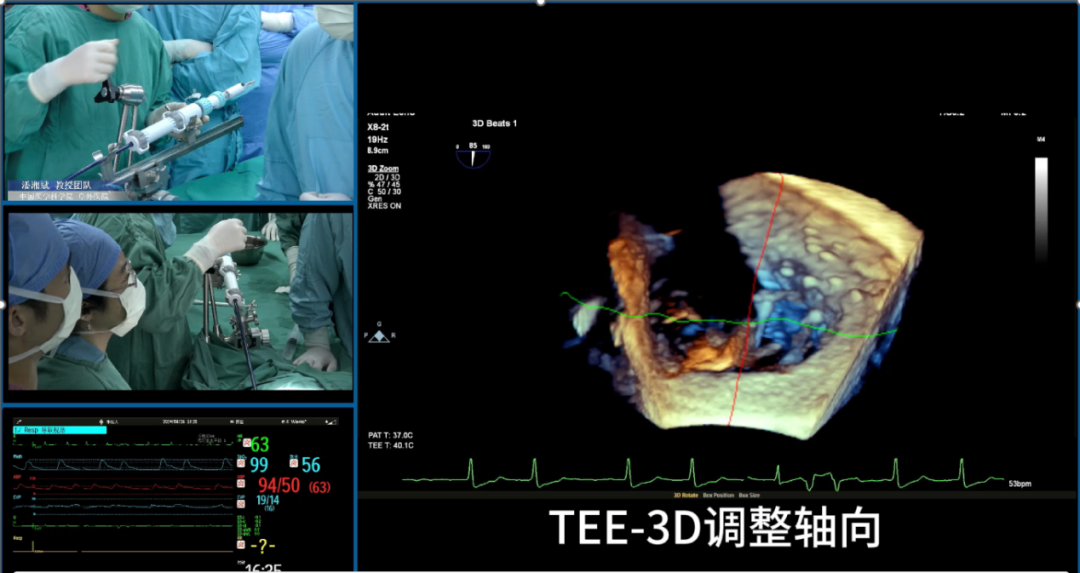

施浩教授介绍了一例成功进行单纯超声引导下经导管三尖瓣置换术的病例,从术前CT评估,术前3D打印体外模拟多方面详细介绍了术前评估流程,并且展示了术中超声过程。

赵广智教授以两例成功进行全超声引导下三尖瓣TEER的病例为例,详细介绍了该技术的术中操作步骤,提供了超声引导三尖瓣TEER的技巧和建议,包括探头操作和多级成像。